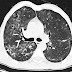

Autosomal Dominant Polycystic Kidney Disease (ADPKD) with Pneumocystic Jerovici (Carinii) Pneumonia

CT axial section of chest lung window in 50 year old male showing diffuse bilateral symmetrical patchy ground glass opacities with areas...